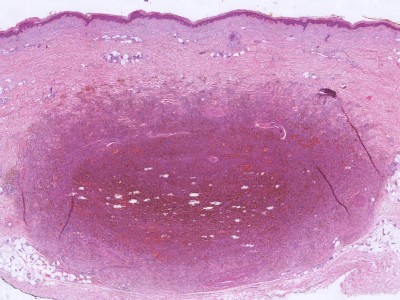

PA:Onder een acanthotische epidermis ziet men irregulaire, spitse papilvorming en woekering van jong, soms basofiel bindweefsel. Er is geen fraaie bundelvorming van het collageen, maar men ziet geïsoleerde vezels in een warrig patroon, soms loodrecht op de epidermis overgang verlopend. Aan de rand is er een geleidelijke overgang in normaal bindweefsel. Het elastine is afgenomen. Het fibroma is zeer rijk aan spoelvormige fibroblasten, soms echter overheersen histiocytaire cellen die ijzer en/of hemosiderine hebben gefagocyteerd (vandaar de naam 'histiocytoma'). Vaak ook zijn er mengvormen met talrijke fibroblasten en histiocyten. Ook vet komt er veel in voor. Deze cellen en hun inhoud (vet en/of ijzer) bepalen de kleurvarianten. Een enkele keer gaan de histiocyten in schimachtige reuzencellen over en lijken ze op Touton cellen (zie xanthomen). Soms is er een beduidende nieuwvorming van capillairen.

Zie ook de

ingescande PA-coupe van de

afdeling pathologie van de University of

Toronto.